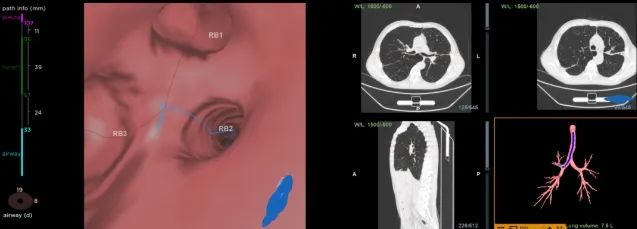

术中操作

术前热蒸汽消融路径评估

术前,门雪琳主任带领团队结合患者疾病情况进行充分的术前讨论,为两位患者制定详细的治疗方案。术中,在全麻下对患者的靶肺段进行热蒸汽消融,手术过程顺利,20分钟左右便完成靶肺段的治疗。患者术后无明显不适,感觉良好。

术中蒸汽消融治疗

治疗后镜下靶肺段